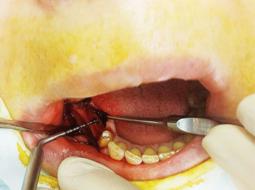

Лечение: Принято решение о пересадки ее собственной кости из угла челюсти. Отслоение слизисто-надкостничного лоскута. Забор блока кости в области угла челюсти. Остеопластика блоками + ксенографт. Установка двух имплантов. Наложение швов.

Результаты лечения: Наращивание объема кости до 10 мм. Фиксация имплантов при недостатки костной массы.